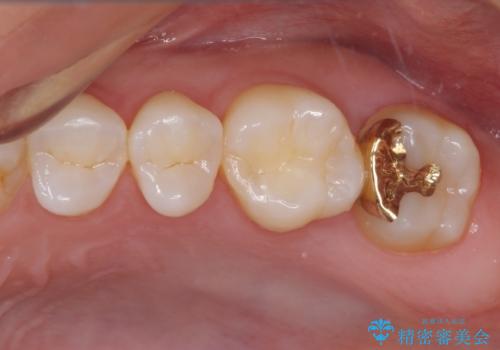

処置後に痛みを感じることはなく、冷たいものがしみることもなくなりました。

奥の大臼歯にもむし歯があったので、一緒に処置を行いました。